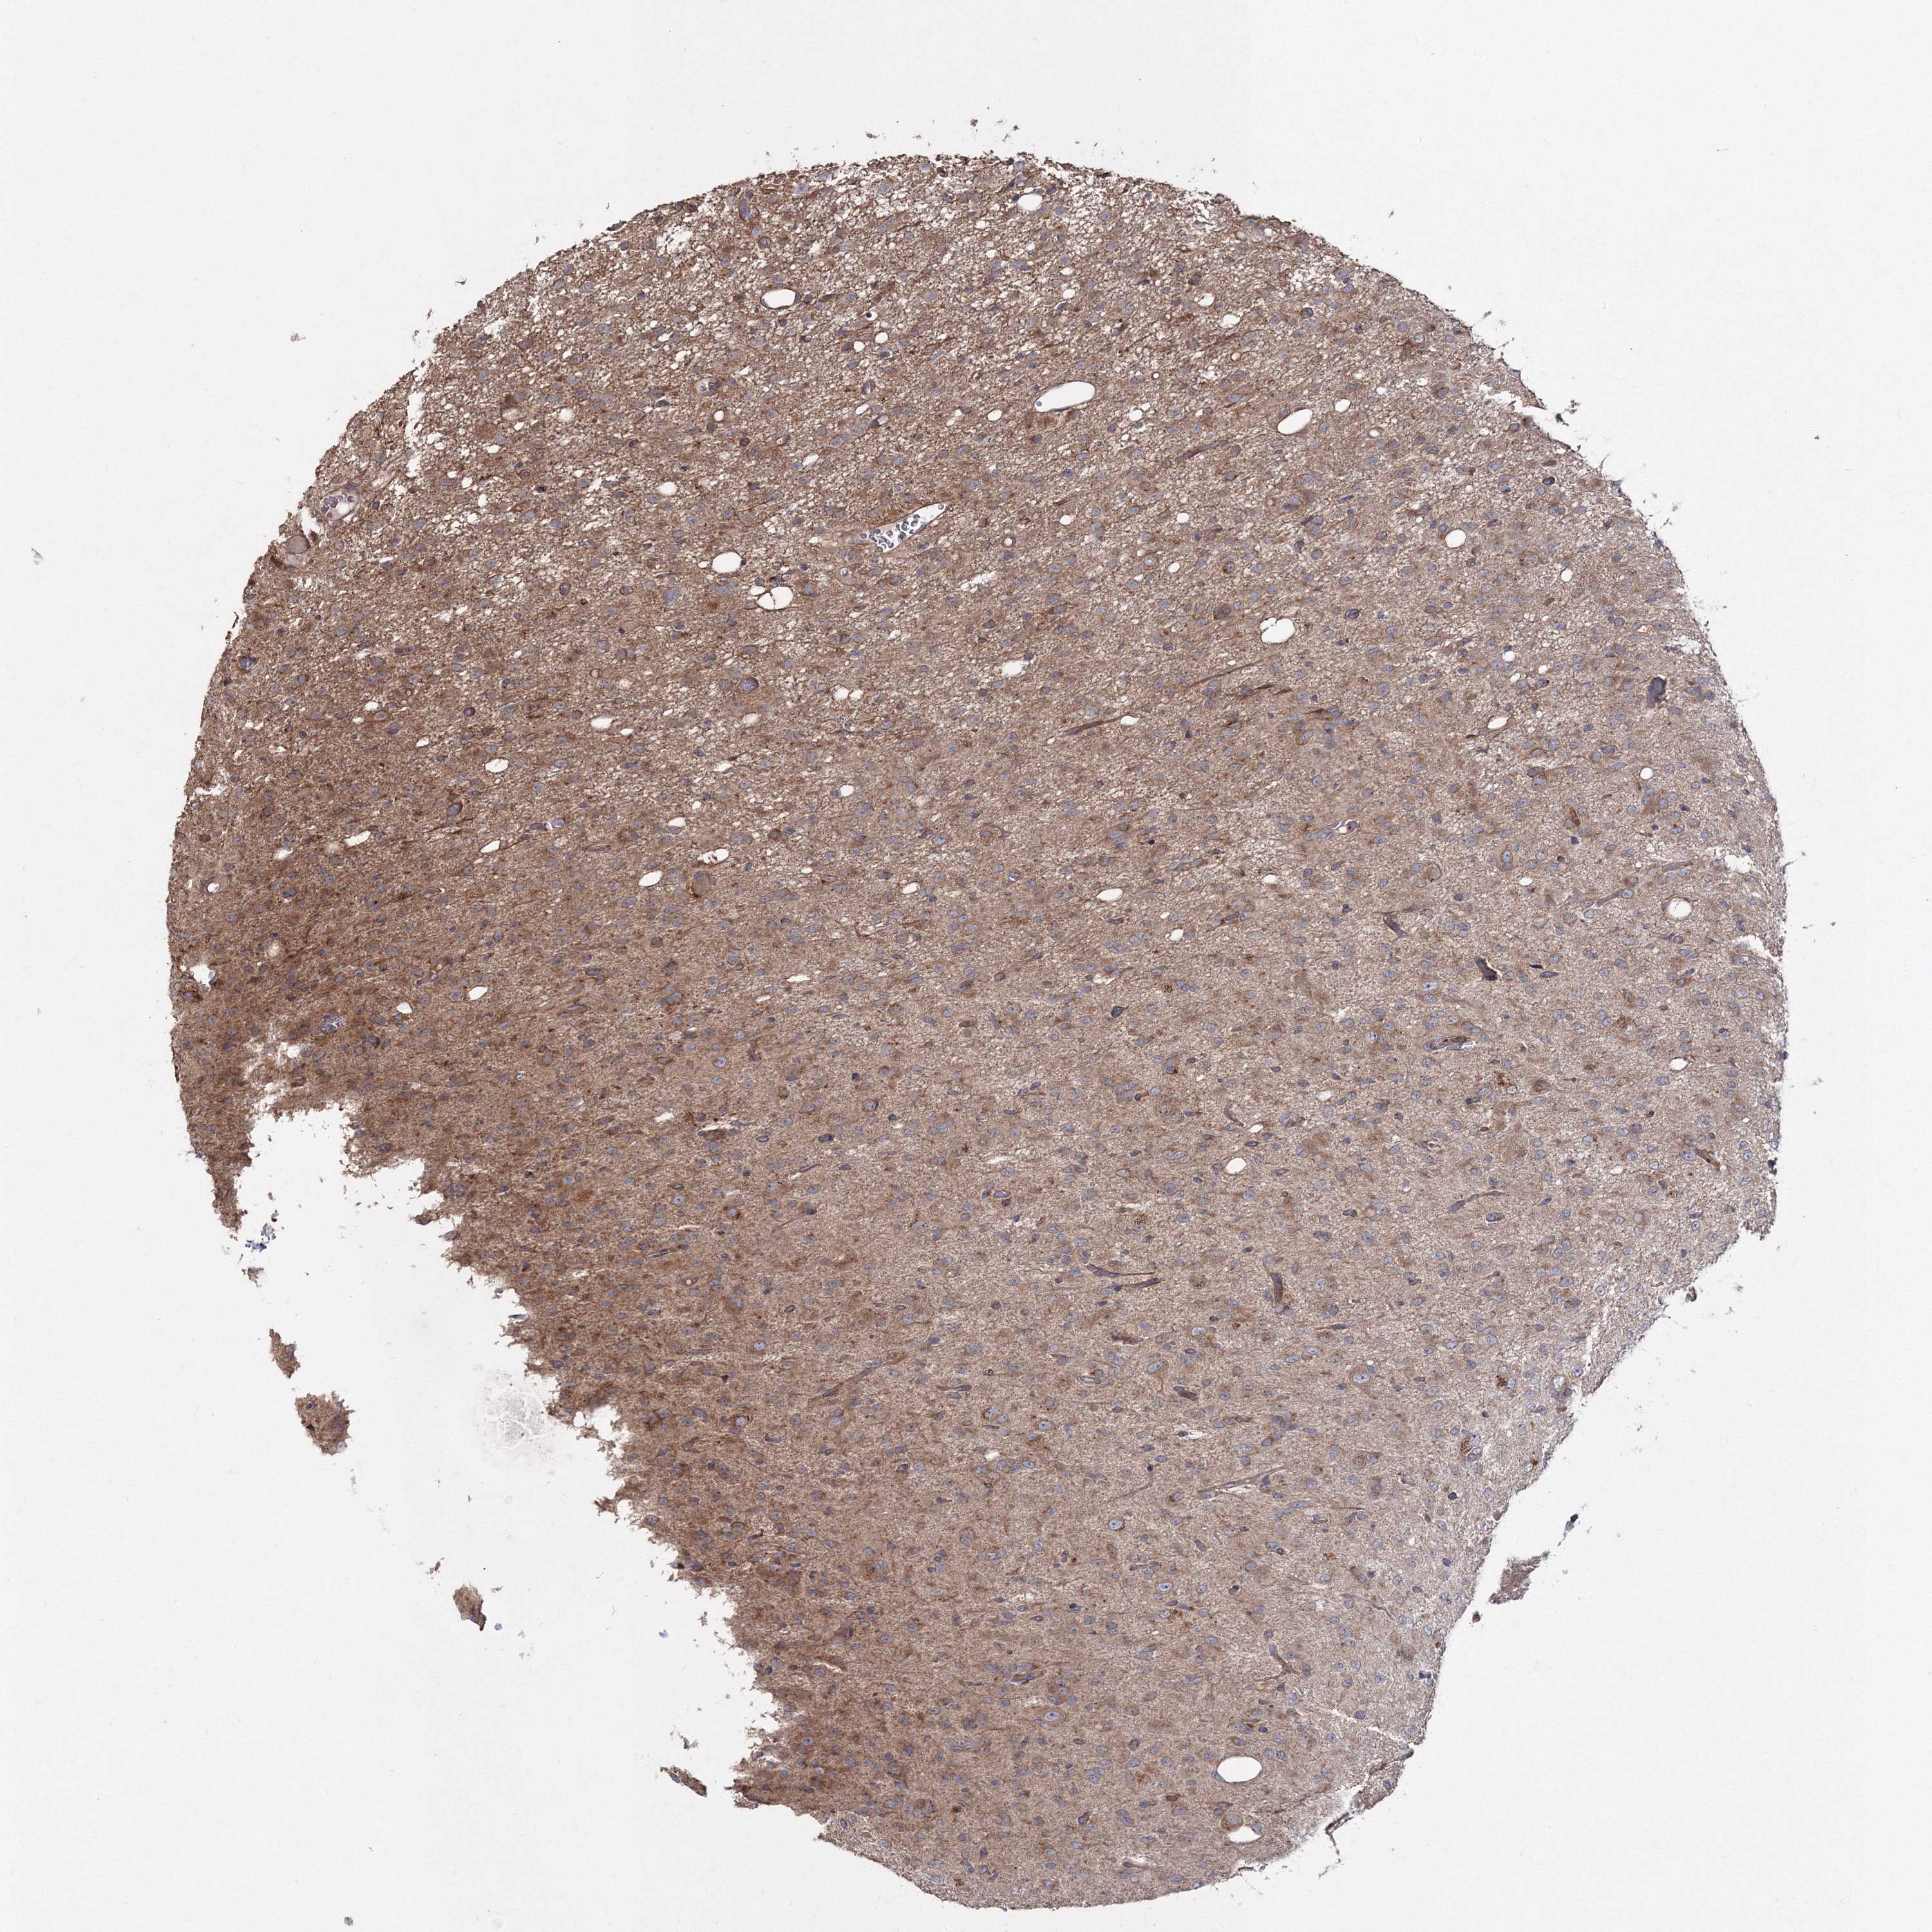

GLIOMA - Protein expressioni

A mouse-over function shows sample information and annotation data. Click on an image to view it in a full screen mode. Samples can be filtered based on level of antibody staining by selecting one or several of the following categories: high, medium, low and not detected. The assay and annotation is described here.

Note that samples used for immunohistochemistry by the Human Protein Atlas do not correspond to samples in the TCGA dataset.

Antibody stainingi

Antibody staining in the annotated cell types in the current human tissue is reported as not detected, low, medium, or high, based on conventional immunohistochemistry profiling in selected tissues. This score is based on the combination of the staining intensity and fraction of stained cells.

Each image is clickable and will lead to virtual microscopy that enables deeper exploration of all samples and also displays staining intensity scores, fraction scores and subcellular localization as well as patient and tissue information for each sample.

Antibody HPA037525

Antibody HPA037526

Staining

High

Medium

Low

Not detected

Intensity

Strong

Moderate

Weak

Negative

Quantity

>75%

75%-25%

<25%

None

Location

Nuclear

Cytoplasmic/membranous

Cytoplasmic/membranous,nuclear

Glioma, malignant, Low grade

Glioma, malignant, High grade

Glioblastoma, NOS